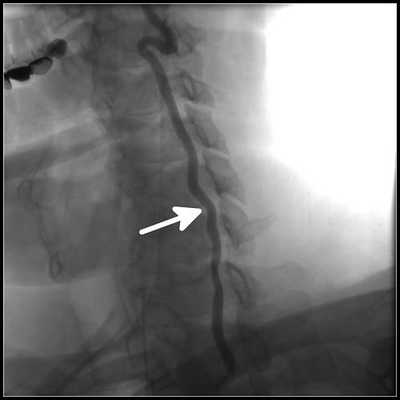

- Транскраниальная допплерография для оценки вертебробазилярной недостаточности.

- Ангиография - рентгенологическая методика, которая показывает нарушение кровотока в расположенных глубоко сосудах.